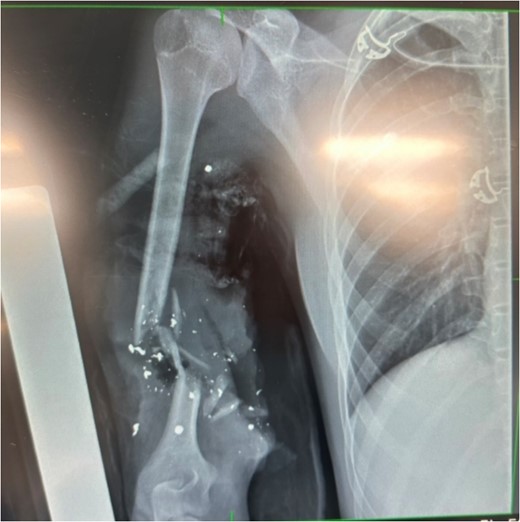

(v) Comminuted humeral fracture (Fig. 3).

X-ray showing extent of damage to humerus; bullet shrapnel visible.